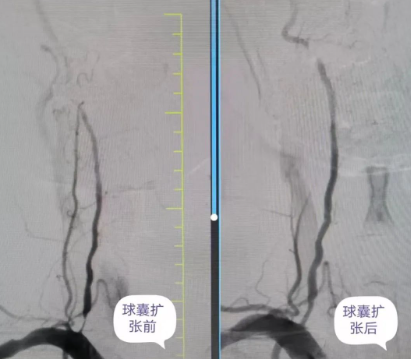

品質(zhì)國文丨精準微創(chuàng) 打通大腦“生命線” ——椎動脈球囊擴張成形術(shù)

近日,國文醫(yī)院公主嶺院區(qū)神經(jīng)介入科丁金明主任、朱洪波副主任帶領(lǐng)團隊為一位右側(cè)椎動脈起始段重度狹窄患者行球囊擴張成形術(shù),成功開通幾近閉塞血管,打通患者“生命通道”,該項技術(shù)自開展以來已為本地區(qū)眾多動脈狹窄患者帶來福音。 閱讀量:1318

品質(zhì)國文 | 精準“疏堵”,為生命“通路”——椎動脈狹窄球囊擴張術(shù)

家住內(nèi)蒙古的閆大哥,近三個月來飽受頭暈困擾,反復(fù)住院治療卻無明顯好轉(zhuǎn),癥狀逐漸加重,甚至出現(xiàn)走路不穩(wěn)的情況。慕名來到長春國文醫(yī)院后,經(jīng)過詳細檢查,發(fā)現(xiàn)閆大哥左側(cè)椎動脈已經(jīng)閉塞 閱讀量:1324